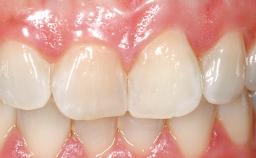

Late Flapless Placement of an Implant in a Maxillary Left Central Incisor Site

A 39-year-old male patient presented with a chief complaint of discomfort and gingival discoloration around his maxillary left central incisor. He was in good general health and was a non-smoker. His past dental history was significant because of the traumatic fracture of tooth 21 in a sporting accident at age 13. Initial dental treatment included endodontic therapy and a full-coverage restoration. The patient became symptomatic 5 years later, when structural failure of the tooth resulted in the dislodgment of the crown. Endodontic retreatment, apical surgery, and post-and-core restoration were performed.

Prosthesis Type FDP

Defining Characteristics One missing tooth to be replaced by an implant-borne crown